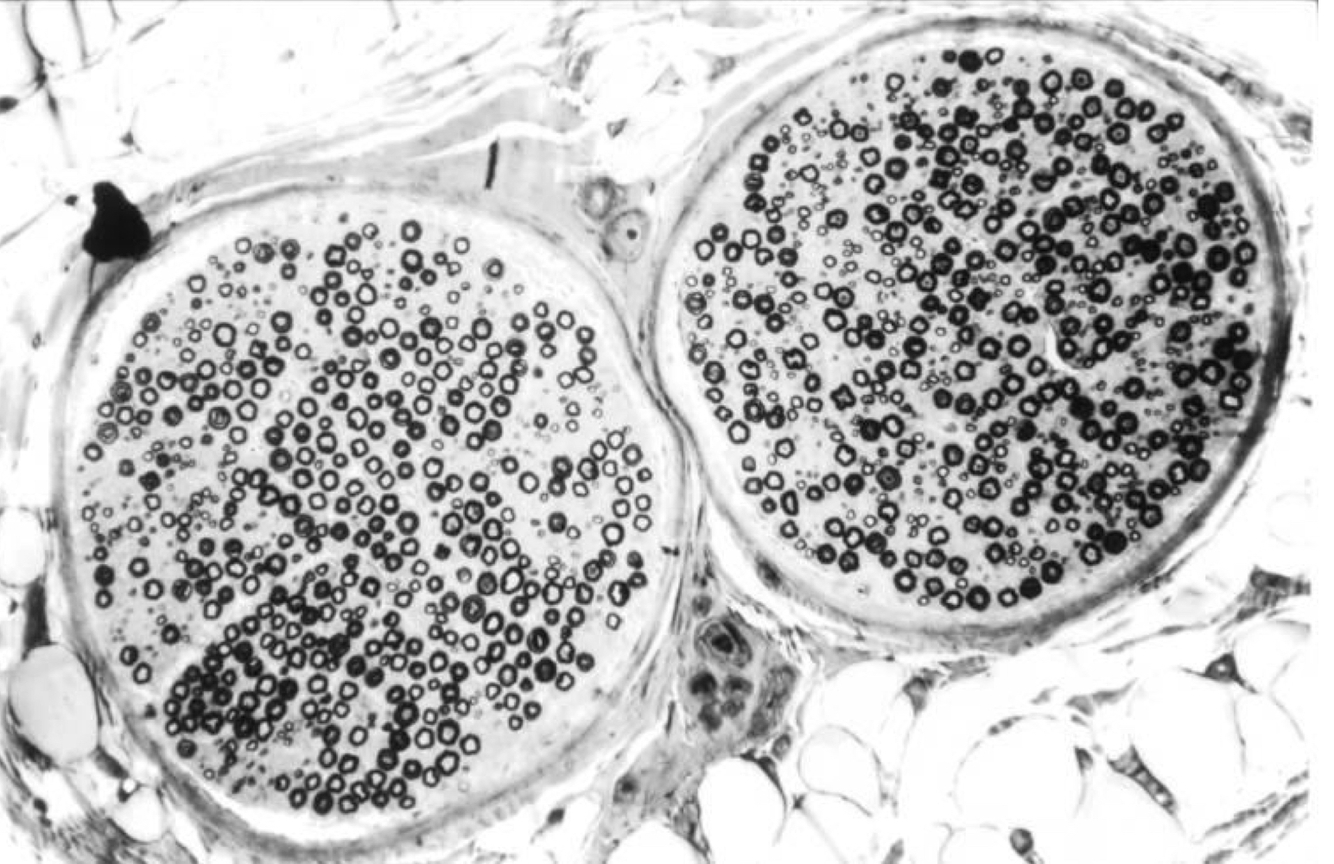

Nerve fascicle, H&E:

• epineurium: entire neuron

• perineurium: multiple fascicles

• endoneurium: one fascicle